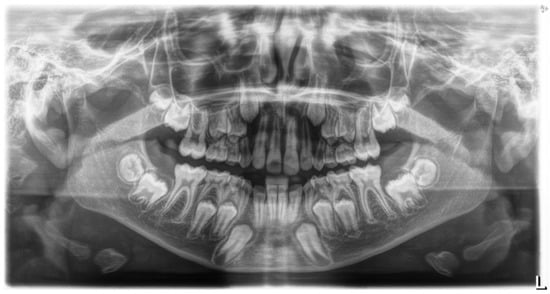

4. Case Report

- Canine angle to the midline;

- Horizontal position of the canine root apex;

- Vertical height of the canine crown;

- Canine overlap of adjacent tooth;

- Buccal–lingual position of the canine.

4.1. Phase 1: Initial Orthodontic Treatment